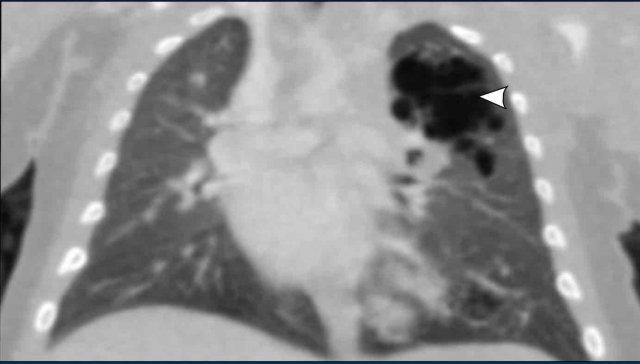

Hình ảnh của một trẻ sơ sinh, 40 tuần tuổi thai.

Nghi ngờ trước sinh có CPAM lớn ở bên trái.

Lúc sinh có suy hô hấp

Hình ảnh

Phim X-quang cho thấy một tổn thương mờ đục hình tròn lớn.

Di lệch nặng các cấu trúc đường giữa kèm xẹp phổi phải.

Ống nội khí quản ở vị trí sâu. Ống thông dạ dày tại chỗ.

Do cần can thiệp trực tiếp, CT có tiêm thuốc cản quang tĩnh mạch đã được thực hiện.

CT cho thấy một tổn thương dạng nang lớn ở thùy trên phổi trái, với sự di lệch của các cấu trúc mạch máu và phế quản.

Tổn thương không có liên quan đến bất kỳ mạch máu hệ thống nào, điều này loại trừ khả năng phổi biệt lập.

Đây là CPAM (dị dạng tuyến nang bẩm sinh của phổi), chưa được thông khí.